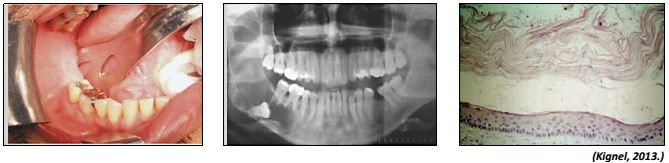

Observe as imagens a seguir referentes à mesma lesão.

Trata-se de um cisto com critérios histológicos bem definidos, com alta taxa de recidiva. Origina-se a partir de remanescentes da lâmina dentária. Geralmente possui comportamento benigno, porém agressivo. Apresenta-se em qualquer idade, com maior incidência entre a 2 e 3 décadas de vida, raramente abaixo dos 10 anos de idade. A mandíbula é invariavelmente mais afetada que a maxila. Sua tendência de crescimento é ocupar os espaços medulares gerando pouca expansão óssea. As informações se referem ao cisto: